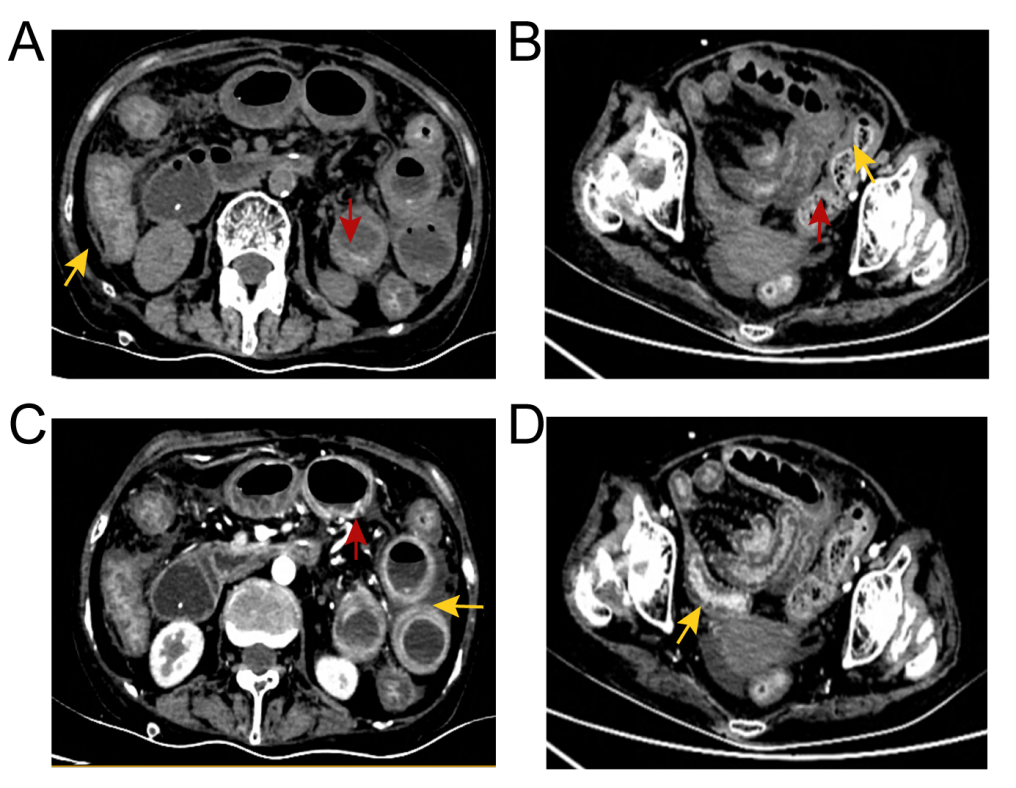

Ò»Ãû63Ë껼ÕßÈëԺǰÓÉÓÚ¼²²¡Ê·ºã¾Ã·þÓÃÃâÒßÒÖÖÆ¼Á¡£ÈëԺʱ£¬»¼ÕßÖ÷ËßʳÓû²»Õñ¡¢¶ñÐÄ¡¢ÍÂÄæ¡¢¸¹Õ͵ÈÖ¢×´ÒÑÒ»Á¬½üÒ»ÖÜ¡£ ¾Ìå¸ñ¼ì²éÏÔʾ£ºË«ÏÂÖ«Ë®Öס¢³¦Ãù΢Èõ¡¢¸¹²¿Ñ¹ÕÍ¡£¼ì²éÀú³ÌÖУ¬»¼ÕßËÄ֫δ¼û¼¡Èâѹʹ£¬¼¡ËἤøˮƽδÓÐÏÔ×ÅÒì³££¬É¨³ý¼¡Ñ׿ÉÄÜ£»Ë«·ÎºôÎüÒôÇåÎúÇÒÎÞ¸ÉʪÔÓÒô£»¸ÎÉö¹¦Ð§Ö¸±êÕý³££¬B³¬Ò²ÏÔʾ¸ÎÔà¾ÞϸÐÎ̬Õý³££¬ÃܶÈÔȳƣ»³¬ÉùÐĶ¯Í¼ÎÞÒì³££¬ÐÄÔàËõ¶ÌºÍÊæÕŹ¦Ð§Õý³££¬¾ùÓë¼ÈÍù±¨µÀA. algeareѬȾµÄÁÙ´²±íÐͲ»·û¡£ »¼Õß½ÓÊÜ¡°³¦¹£×衱µÄÖÎÁƼƻ®£¬ÔÚÖÎÁƽ׶ÎÖи¹ÕͼÓÖØ£¬²¡Çé½øÒ»²½¶ñ»¯¡£ ¸¹²¿ÅÌËã»ú¶Ï²ãɨÃèµÄ´ú±íÐÔͼÏñ¡£»ÆÉ«¼ýÍ·ÏÔʾ³¦±ÚÔöºñºÍճĤˮÖ×£»ºìÉ«¼ýÍ·ÏÔʾð¤Ä¤³äѪ£»³¦±ÚÖÜΧģºýµÄÖ¬·¾¼ä϶Åú×¢¸¹Ç»»ýÒº¡£

¸¹²¿ÅÌËã»ú¶Ï²ãɨÃè(CT)ÏÔʾ¸ÎÔà¡¢µ¨ÄÒ¡¢ÉöÔà¡¢ÒÈÏÙ¡¢×Ó¹¬ºÍ°òë×δ¼ûÒìÑù£¬µ«³¦±ÚÔöºñ£¬³¦±ÚÖÜΧ֬·¾¿Õ¼äÄ£ºý£¬Õ³Ä¤Ë®Ö×£¬¸¹Ç»ÖдæÓдó×Ú¸¹Ë®¡£ÓÚÊÇ£¬ÔÚ³¬ÉùÖ¸µ¼Ï¶Ի¼ÕßÐи¹Ç»´©´ÌºÍ¸¹Ë®ÒýÁ÷¡£¸¹Ë®Ñù±¾µÄ¿¹ËáȾɫ¡¢Î¢ÉúÎï×÷Óý£¨Ï¸¾úºÍÕæ¾ú£©¼°Ï¸°û²¡ÀíѧЧ¹û¾ùΪÒõÐÔ¡£